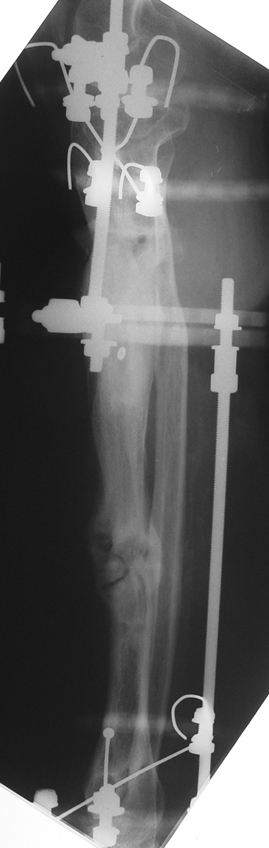

Recently, ilizarov techniques which is basis depend on distraction osteogenesis , bone segment transport or acute shortening after the resection at the site of pseudarthrosis combined with lengthening at another level of bone have been used. These treatment techniques may include some advantage for problems of infection, leg-length discrepancy, soft-tissue loss, and joint contracture.

Case 2